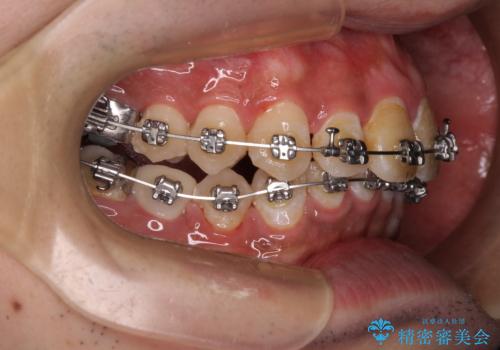

- 矯正装置

- メタルブラケット

- 主張してる上の前歯を気にして来院された患者様です。

上の前歯が出ているものの、口元が出っ歯というわけではなかったため、非抜歯矯正にて治療を行うこととしました。

下顎に対して上顎歯列が全体的に前方に位置しており、特に右側の奥歯の咬み合わせの前後のズレが大きいため、補助装置を用いて咬み合わせを改善することとしました。